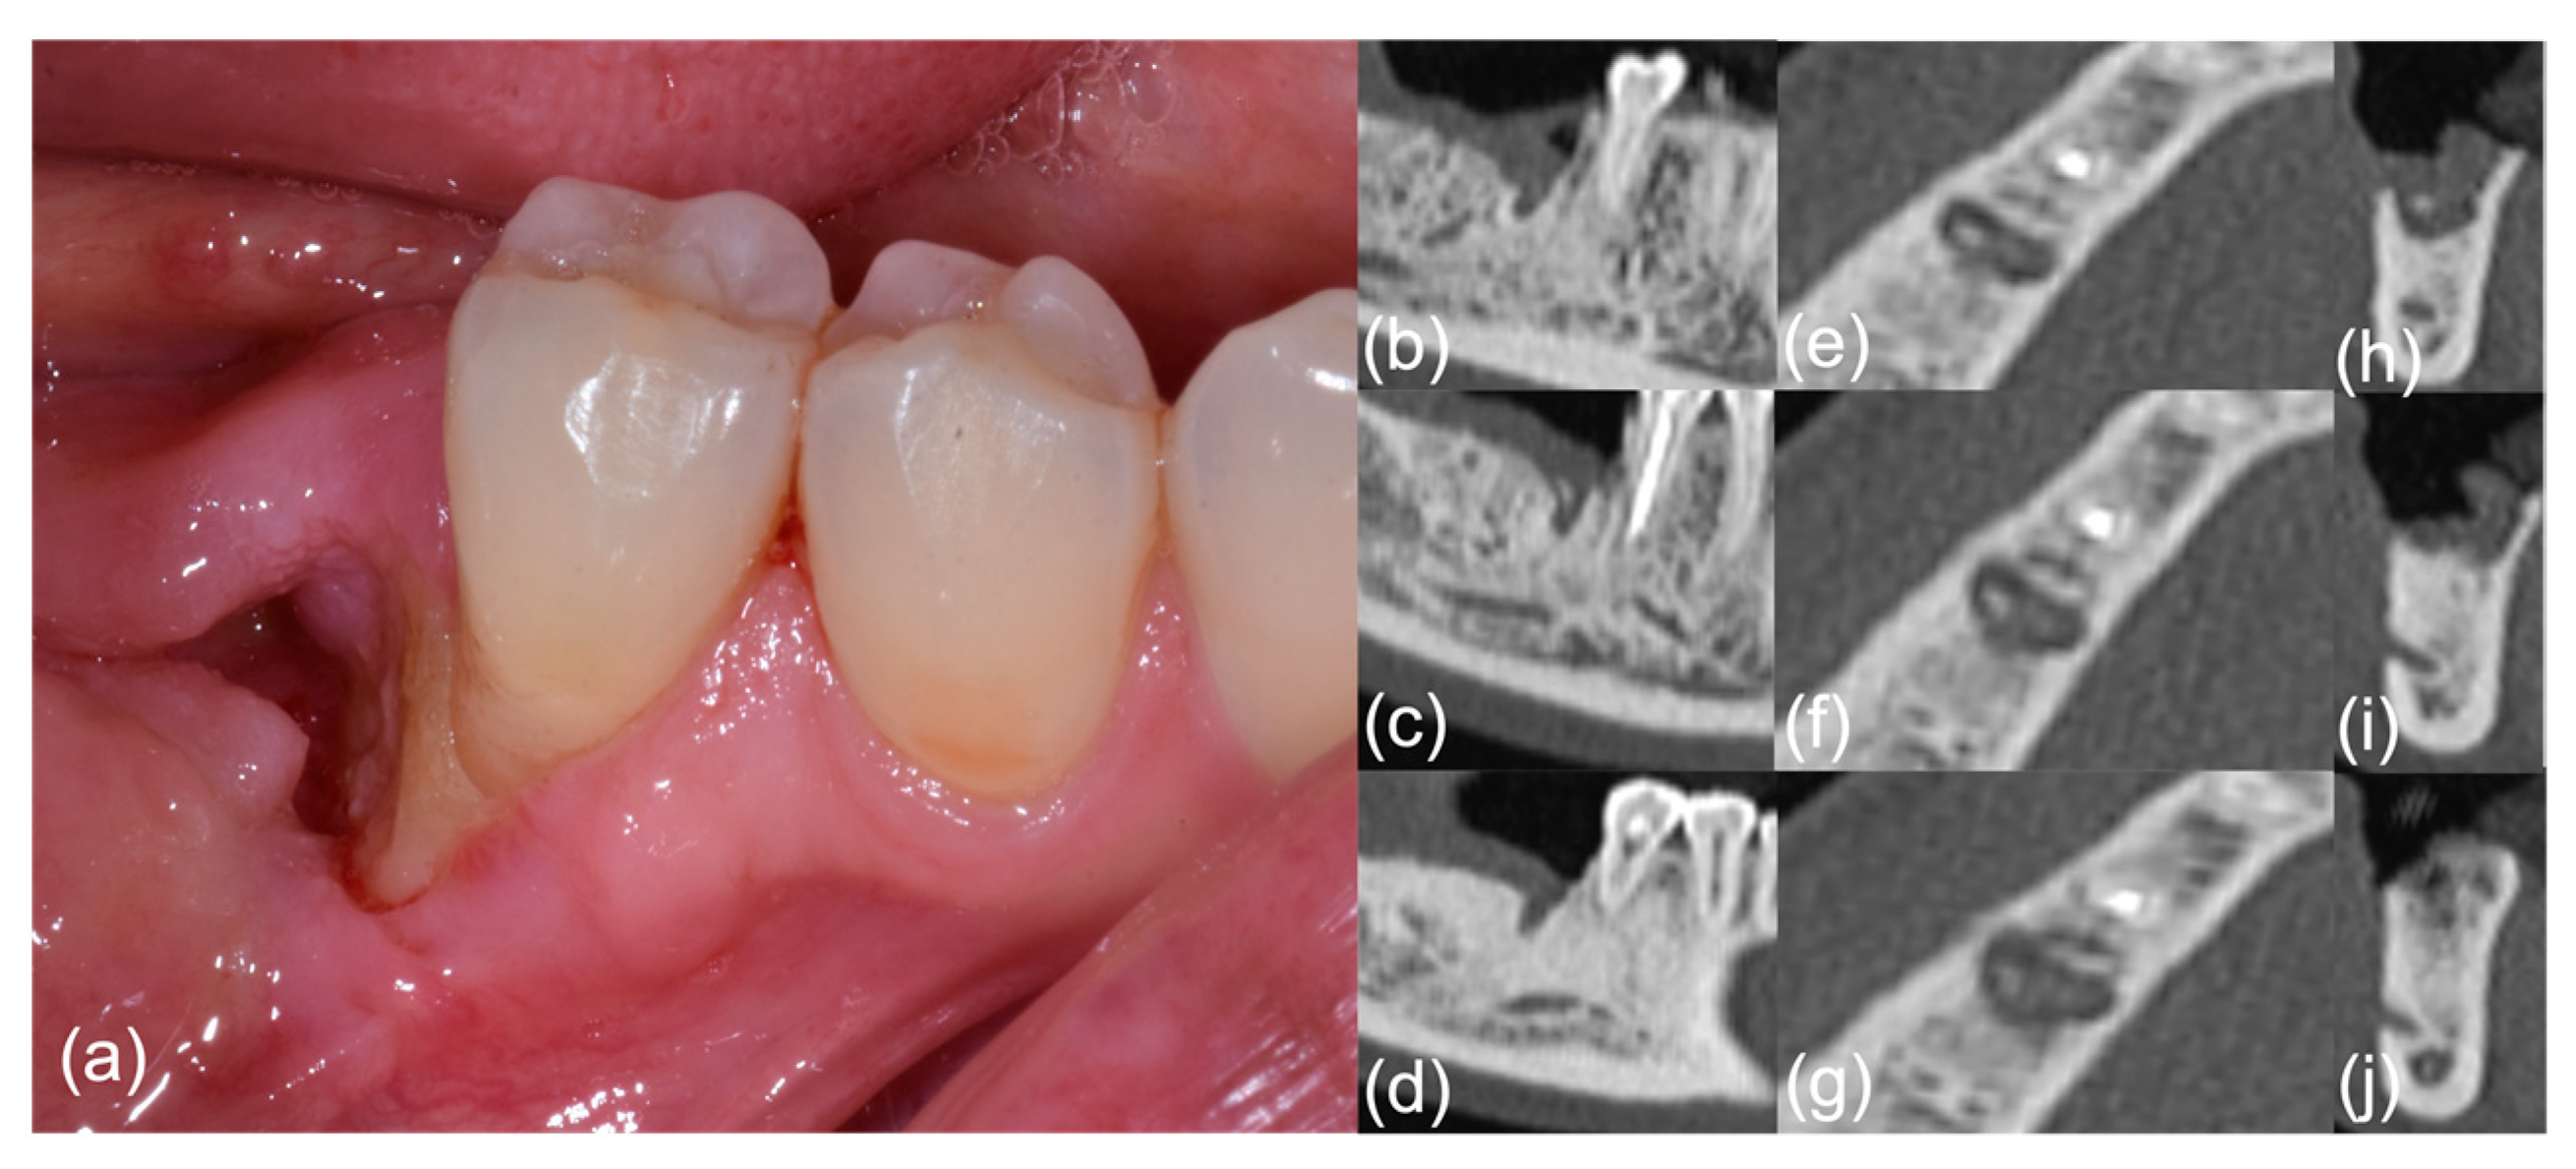

| #1 | E Pu P | 8 | II | Ground glass disappearance (improvement) | No pain/no ONJ signs | n.a. | n.a. |

| #2 | E Pu P | 7 | II | Bone healing (improvement) | No pain/no ONJ signs | Stable (improvement) | No pain/no ONJ signs |

| #3 | Pu S Pa P | 10 | II | Slightly improved bone formation with persistent ground glass (improvement) | No pain/no ONJ signs | Bone formation (improvement) | No pain/no ONJ signs |

| #4 | A E P | 10 | II | Slightly improved bone formation (improvement) | No pain/no ONJ signs | Periosteal reaction (improvement) | No pain/no ONJ signs |

| #5 | F E P | 7 | II | Slightly improved bone formation (improvement) | No pain/no ONJ signs | Stable (improvement) | No pain/no ONJ signs |

| #6 | De E P | 6 | II | Slightly improved bone formation (improvement) | No pain/no ONJ signs | Stable (improvement) | No pain/no ONJ signs |

| #7 | F E D | 7 | II | Slightly improved bone formation (improvement) | No pain/no ONJ signs | n.a. | n.a. |